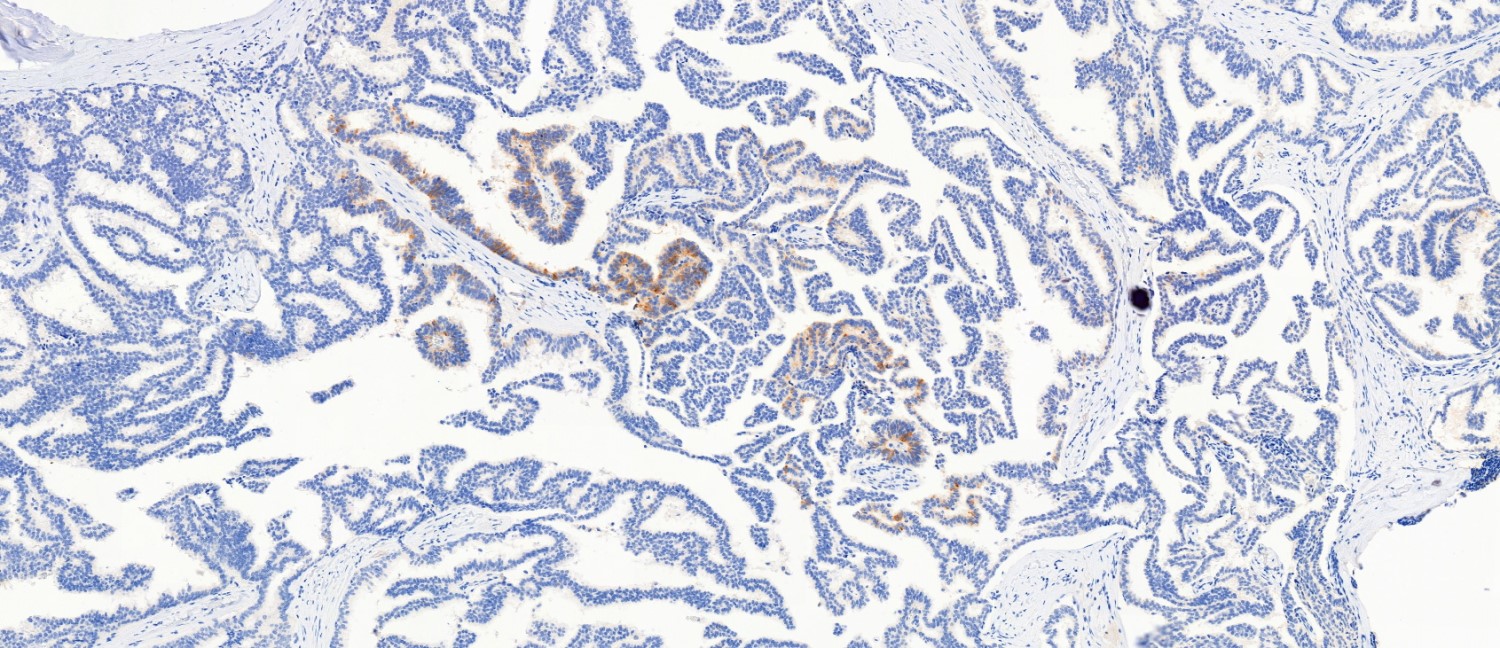

- Most show complete lack of myoepithelial cells along the papillae and around the periphery of the tumor (Am J Surg Pathol 2006;30:1002, Am J Surg Pathol 2011;35:1)

Microscopic (histologic) images

Contributed by Kristen E. Muller, D.O. , Mariel Molina Nunez, M.D. and Julie Jorns, M.D. (Case #518)

Positive stains

- ER and PR (strong, diffuse) (Curr Probl Cancer 2018;42:291, Mod Pathol 2021;34:1044)

Negative stains

- Myoepithelial markers (i.e., p63, calponin, actin, smooth muscle myosin heavy chain, CD10) negative within papillae and around the tumor or focally present at the periphery of the lesion (Am J Surg Pathol 2006;30:1002, Am J Surg Pathol 2011;35:1, Curr Probl Cancer 2018;42:291)

- HER2